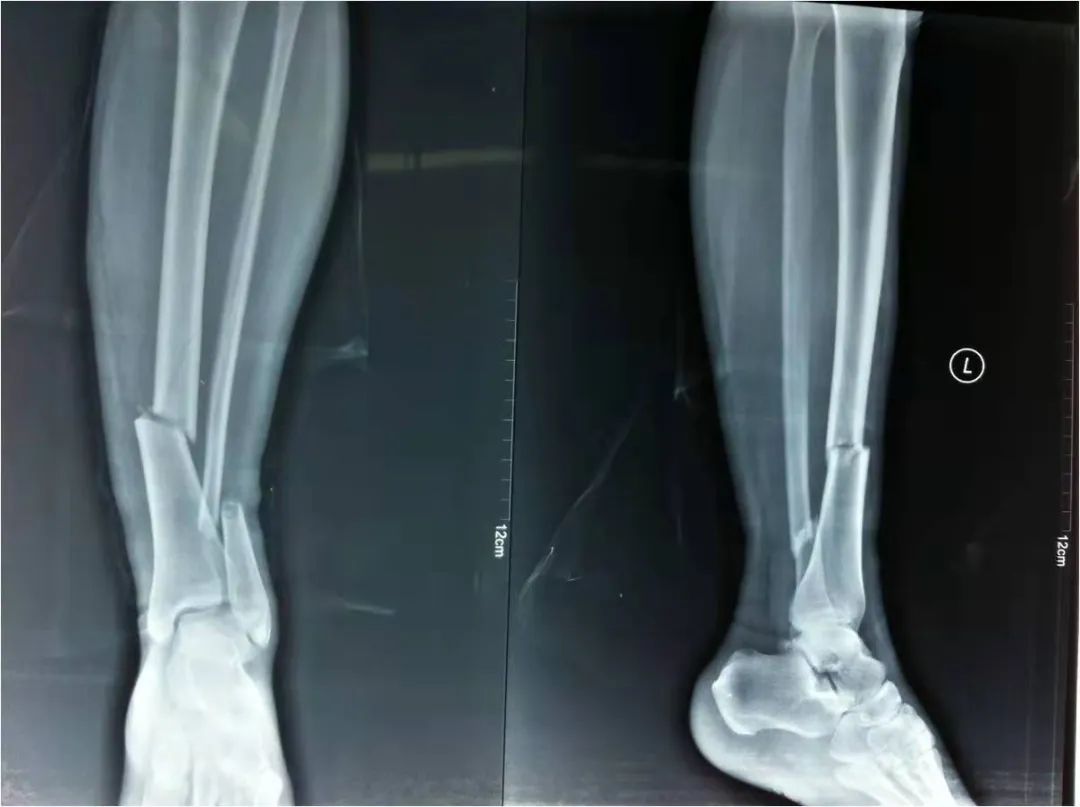

2022年4月22日,我院急救中心接診了一名骨折患者:患者在家不慎摔倒,導致剛做完手術(shù)沒多久的脛腓骨再次受創(chuàng),疼痛劇烈傷情加重。骨科呂國福主任迅速給予夾板外固定治療,并給予止疼治療減輕患者疼痛。經(jīng)診斷患者脛腓骨粉碎性骨折明確,且第一次接骨板釘?shù)廊钥梢?,如不及時手術(shù)可能出現(xiàn)骨斷端外露發(fā)展為開放性骨折,可能出現(xiàn)骨筋膜室綜合癥。

如采用傳統(tǒng)手術(shù)需大范圍剝離軟組織,手術(shù)切口在18公分,損傷面大,影響骨折愈合。經(jīng)過科內(nèi)術(shù)前討論后與患者及家屬溝通后,呂國福主任決定行小切口微創(chuàng)鈦板植入內(nèi)固定手術(shù)治療,術(shù)中植入內(nèi)固定物并剝離軟組織,此方法對周圍皮膚破壞小,手術(shù)切口最小僅0.5公分,極大降低皮膚壞死及后期出現(xiàn)骨不連發(fā)生幾率,從而達到解剖復位。